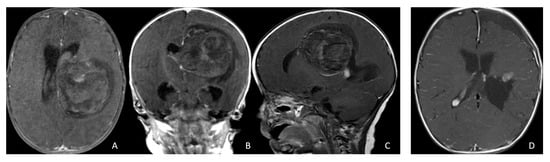

The cerebellar peduncular, vermis, and CPA/CMF are common site of ATRTs. Most ATRT-TYR tumors arise from the middle cerebellar peduncle and inferior vermis [76] and can extend exophytically into the cerebellopontine angle (CPA) and cerebellomedullary fissure (CMF). ATRT-MYC tumors can originate from cranial nerves in the CPA, producing imaging appearances that overlap with TYR tumors; however, the age distribution differs, with TYR typically affecting much younger children than MYC. Infratentorial ATRTs frequently mimic posterior fossa ependymomas in their location and propensity to extend into the CPA and fourth ventricle, but ATRTs tend to be more infiltrative, whereas ependymomas are usually expansile and less invasive [77]. Consistent with this pattern, the European Rhabdoid Registry reports cranial nerve involvement occurs in approximately 3% of ATRT cases and is most often associated with the MYC subgroup [62]. One female patient with CPA ATRT of CPA, who was notably the oldest in this cohort, had a tumor that likely originated from the vestibular nerve, without involvement of the brainstem or cerebellum. (Figure 12).

Figure 12.

CPA ATRT. (A–D): MR images ((A): axial; (B): coronal) of a 20-year-old girl, the oldest in this cohort, who presented with left-sided hearing loss and partial facial weakness, reveal ATRT that appears to originate from the vestibular nerve. Surgical findings and post-resection MR images ((C): axial; (D): coronal) indicate no tumor invasion into the cerebellum or brainstem, which contrasts with typical presentations of infantile ATRT.